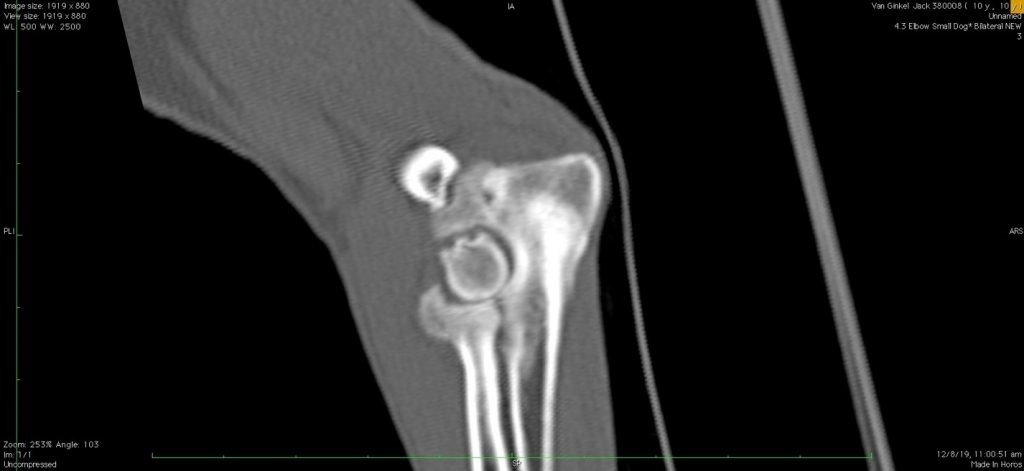

Veterinarians can diagnose arthritis through a combination of physical examinations, observations and diagnostic imaging. X-rays let them assess joint damage and rule out any other potential causes of the symptoms.In some cases, advanced imaging techniques like MRIs or CT scans might be necessary to get a more detailed view of the joints.

2D CT scan showing severely arthritic elbow